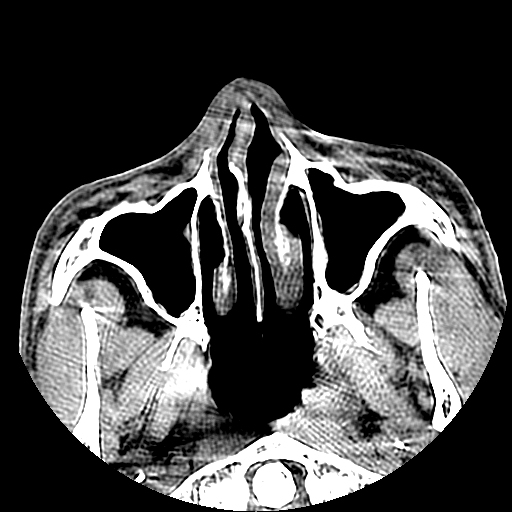

以下是引用liaoqiang在2008-7-16 21:15:00的发言:[br]右侧鼻骨骨折

以下是引用zxd95在2008-7-16 21:39:00的发言:[br]右侧上颌骨额突骨折。[br][br][br][br]